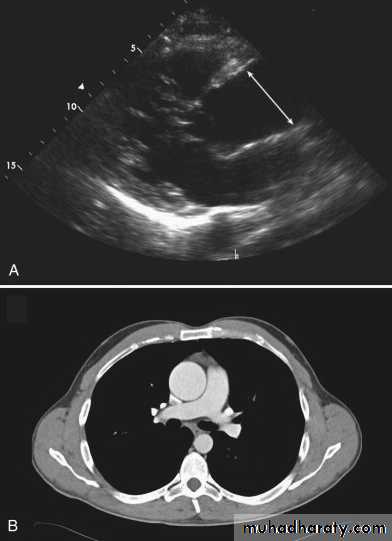

InvestigationsDoppler echocardiography may show aortic regurgitation, a dilated aortic root and, occasionally, the flap of the dissection. Transoesophageal echocardiography is particularly helpful because transthoracic echocardiography can only image the first 3-4 cm of the ascending aorta. CT and MRI are both highly specific, and angiography of the aortic arch is not usually required unless these techniques are not available.

Chest radiography, echocardiography, MRI or CT may detect aortic dilatation at an early stage and can be used to monitor the disease.